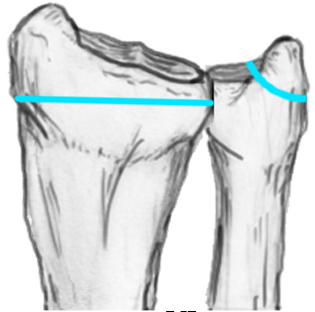

Distal Radius Angles

- radial volar tilt 11°

- radial inclination  22°

- radius is 11 mm longer than ulna

- ulna variance 2mm positive on average

Distal Radius NormalNormal Radial InclinationNormal Radial Length

3.   Radial shortening > 5 mm

4.  Radial inclination < 15o